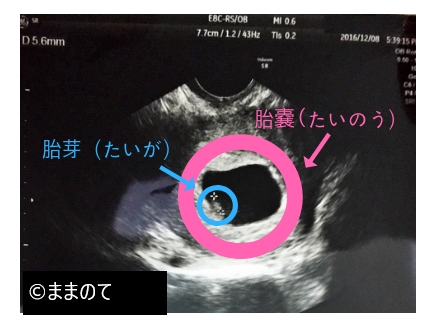

妊娠初期に子宮の中に赤ちゃんを包む「胎嚢(たいのう)」と呼ばれる袋が形成されます。胎嚢はGSと呼ばれることもあります。胎嚢は受精卵が着床した場所に作られ、妊娠を判断する大きな要素となります。胎嚢・胎芽・心拍確認の三点が確認できた時点で、妊娠が成立(確定)します。

胎嚢は妊娠4週のはじめから5週頃にエコー検査で確認でき、5週の前半には胎嚢の中に小さなリングが出現します。このリングは「卵黄嚢(らんおうのう)」と言い、胎盤が完成するまで赤ちゃんに栄養を供給したり、造血したりする役割を担っています。その後、5週の後半から6週頃になると、卵黄嚢に接するようにして胎芽が確認できるようになります。

妊娠6週では、赤ちゃんの頭と胴体の区別がつくようになり、胎嚢の中には胎芽が確認できます。胎嚢の大きさは1.5~2cm程度に成長しています。

経腟超音波検査で胎芽の心拍動を見られるようになるのもこの時期です。心拍が確認されれば、最終月経の開始日や胎芽の頭からお尻までの長さを計測した「胎児頭臀長(とうでんちょう)」から正確な出産予定日を決定します。